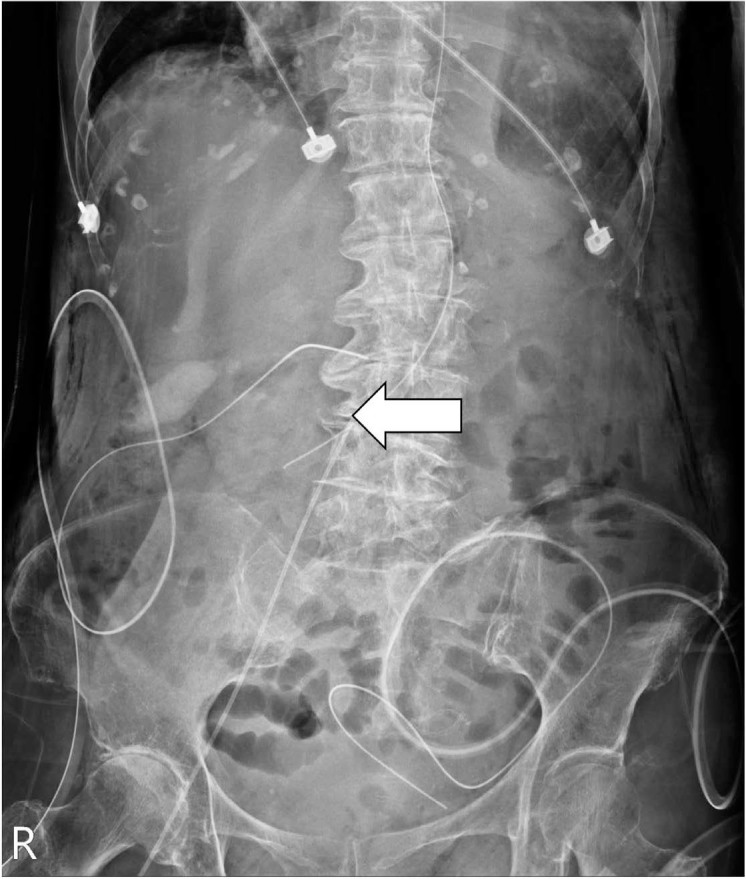

Introduction: Malposition is a relatively rare complication associated with peripherally inserted central catheters (PICCs), particularly in cases of superficial femoral vein (SFV) catheterization. To the best of our knowledge, we are the first to report this rare case of SFV PICC malposition in the contralateral renal vein.

Case presentation: An 82-year-old woman underwent bedside cannulation of the SFV for PICC under ultrasound guidance. Subsequent radiographic examination revealed an unexpected misplacement, with the catheter tip positioned toward the contralateral renal vein. After pulling out the catheter on the basis of the X-ray result, it was observed that the catheter retained its function.

Conclusion: Although rare, tip misplacement should be considered in SFV PICC placement. Prompt correction of the tip position is crucial to prevent catheter malfunction and further catastrophic consequences. For critical patients receiving bedside SFV PICC insertion, postoperational X-ray is crucial for enhancing safety.